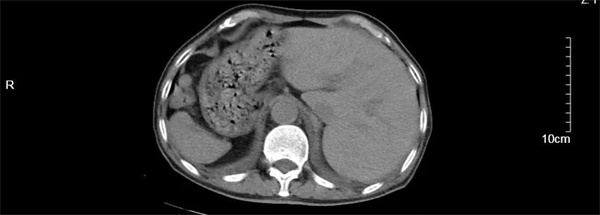

汪大爷因“反复胸闷气喘1周伴头昏”在当地卫生院就诊,心电图检查显示高度-III度房室传导阻滞(心室率40次/分)和镜像右位心心电图。由医共体转诊中心转至我院进一步诊治。入院后,行24小时动态心电图和心脏彩超检查发现,患者不仅患有II度房室传导阻滞,呈2:1下传(最慢心率35次),交界性逸搏伴干扰性房室分离。彩超更是发现汪大爷还是一位罕见的镜面右位心,其心脏及腹腔内脏器官位置与正常人完全相反,如同正常脏器的 “镜中像”,这种先天性畸形的发生几率约为1/100万。